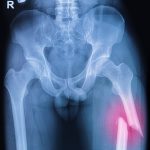

Unlike other bone conditions which are asymptomatic, osteomalacia does present symptoms, such as pain in the bones, muscles weakness, and partial fractures, which are slight cracks in the bones.

To properly diagnose osteomalacia, the doctor must rule out other conditions and uncover the underlying cause. To diagnose osteomalacia, the patient may be referred for blood and urine tests, X-ray, and a bone biopsy.